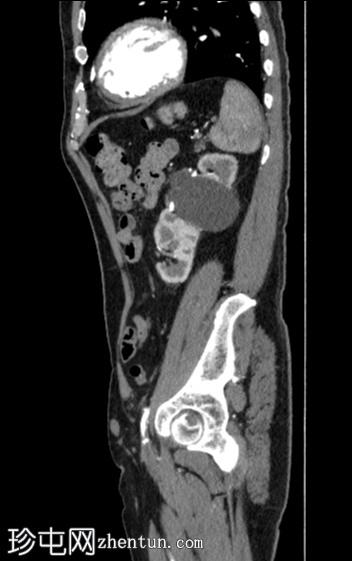

矢状位增强扫描

动脉期

右向左交叉融合性肾异位(轴位、冠状位和矢状位图像),右侧异位肾上极与左侧肾下极融合。

肾皮质囊肿。

主动脉-髂动脉粥样硬化晚期改变。